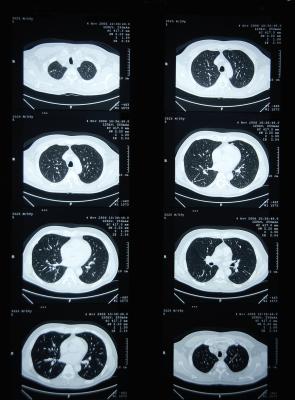

April 27, 2020 — Computed tomography (CT) scans for people at risk for lung cancer lead to earlier diagnoses and improve survival rates, but they can also lead to overtreatment when suspicious nodules turn out to be benign.

A study published in American Journal of Respiratory and Critical Care Medicine indicates that an artificial intelligence strategy can correctly assess and categorize these indeterminate pulmonary nodules (IPNs). When compared to the conventional risk models clinicians currently use, the algorithm developed by the team of researchers in a very large dataset (15,693 nodules) reclassified IPNs into low-risk or high-risk categories in over a third of cancers and benign nodules.

Currently, clinicians refer to guidelines issued by the American College of Radiology and the American College of Chest Physicians. Adherence to these guidelines can be variable, and how patient cases are classified can be subjective. With the goal of providing clinicians with an unbiased assessment tool, the researchers developed an algorithm based on datasets from the National Lung Screening Trial, Vanderbilt University Medical Center and Oxford University Hospital. Their study is the first to validate a risk stratification tool on multiple independent cohorts and to show reclassification performance that is significantly superior to existing risk models.